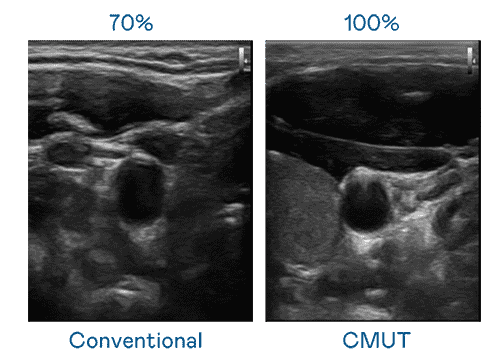

CMUT 技术是一种用电容式微机电元件来产生超音波讯号的技术。。。。与传统 PZT 压电式技术相比,,CMUT 频宽增加 30%,,,更宽频的超音波讯号让影像解析度大幅提升,,,是实现高影像品质医疗超音波扫描、、、、促进精准医疗发展的关键技术。。。。

大频宽带来超清晰影像

超音波影像的解析度高低,,,首先取决于探头能发出的讯号频宽。。。。牛牛游戏 CMUT 可提供高清晰的超音波讯号,,,,提供高频宽、、、、高灵敏度、、、影像纹理细节更高的超音波影像,,协助医护人员缩短影像判读时间及利用精准的医疗影像进行诊断。。